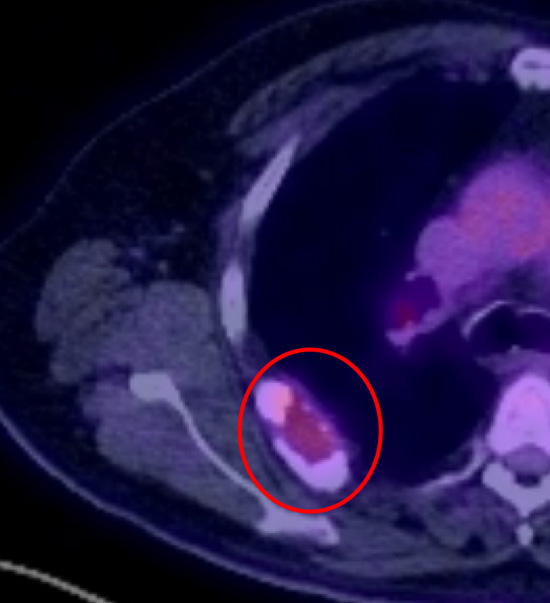

Secondary (metastasis) cancer to the 7th right rib causing pain on moving the shoulder (red rings) on chest CT (left) and PET (right). The original cancer was from the thyroid. The rib and cancer were surgically removed